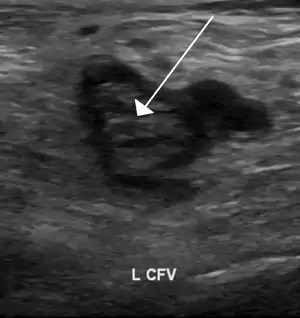

| An ultrasound image demonstrating a blood clot in the left common femoral vein. | |